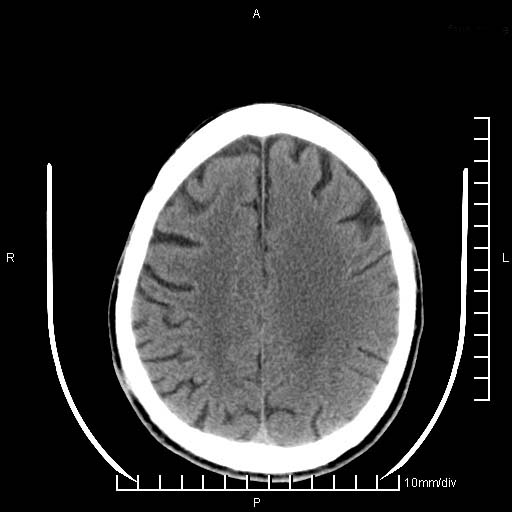

临床以双下肢浮肿,疼痛收治,无明显神经系统症状,既往无梗塞,出血病史。左颞叶见低密度灶,考虑什么?

考虑左侧颞叶脑软化灶。

无强化 无占位 软化灶吧

无强化、 无占位、局部脑沟增宽, 软化灶吧。